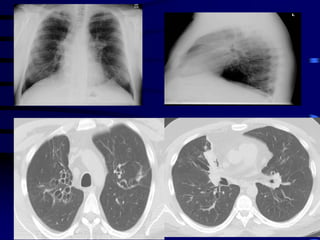

Wheezing in

Children

Adventitious Airway Sounds

 Snoring

 Stridor

 Wheezing

 Crepitations

Airway Diameter

Cause of Wheezing

 Not from obstruction of small airways –

Surface area too large

 From increased intrathoracic pressure +

decreased large airway pressure =

vibration of airway wall in large airways

(Generations 1-5)

Wheezing

 Sign of lower (intra-thoracic) airway

obstruction

 Small airways

Air Trapping

 Hyperinflated chest

 Barrel shaped

 Loss of cardiac dullness

 Liver pushed down

 Hoover sign

Hoover Sign

 Normal diagphragm movement

 Hyperinflation = diaphragm flattened

 Diaphragm contraction = paradoxical

inward movement of lower interrcostal

area during inspiration

Acute Wheezing

 Asthma

 Bronchiolitis

 Foreign body

Bronchiolitis